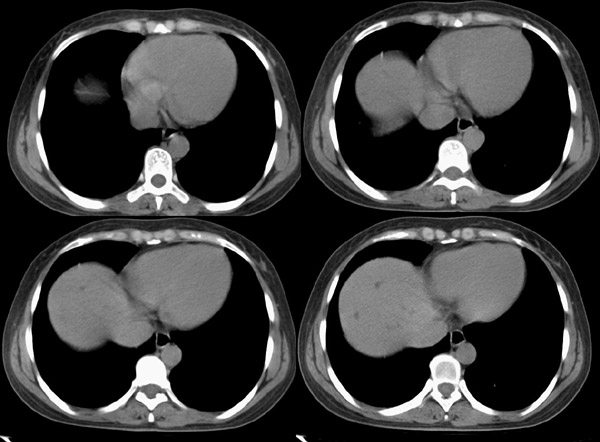

腹部ct平扫:(5mm层厚)

f42y近半月来无明显诱因出现右上腹疼痛之主诉就诊。疼痛多于饭后半小时发作,为持续性隐疼,呈阵发性、刀割样、钻顶样疼痛加剧,且向右肩背部放射,伴恶心、出汗、呕吐,呕吐内容物为胃内容物,无呕血,时有返酸、呃逆、烧心感,无腹胀、腹泻及黑便。时有发冷、发热(但体温不高);呕吐后腹疼稍有缓解,在当地诊所按“胃炎”对症治疗10天,效果不佳。血常规为:白细胞:9、8*109,中性64%,血红蛋白为151g/l,血小板为167*107。 既往有胆道蛔虫病史30余年,曾有呕虫史,否认肝炎及肺结核、溃疡病史。无外伤、手术及药物过敏史,陕西丹凤县四坪镇人,未去过疫区。